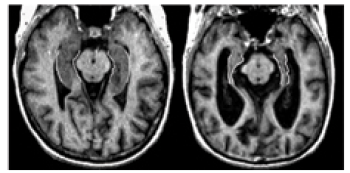

When brain cells degenerate and die, the brain dramatically shrinks in some areas of the brain.

Two MRIs that depict the brain of a person without Alzheimer's, and a person with Alzheimer's.

MRI images courtesy of Sunnybrook and Women's College Health Sciences Centre.

To illustrate, the image here shows that a person who doesn't have Alzheimer's disease (left) has more brain tissue than a person who has Alzheimer's (right).

This shrinkage continues as the disease progresses, affecting the function of the brain and increasing the severity of symptoms.